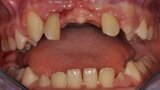

Ryc. 8_Stan miejscowy bezpośrednio przed autotransplantacją.